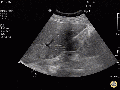

Images

Normal

Abnormal

RUQ

- Landmarks

- Visualize the interface between the liver and kidney

- Scan anterior to posterior identifying Morison’s pouch and the superior and inferior pole of the kidney

Findings

- Anechoic areas between the liver and kidney